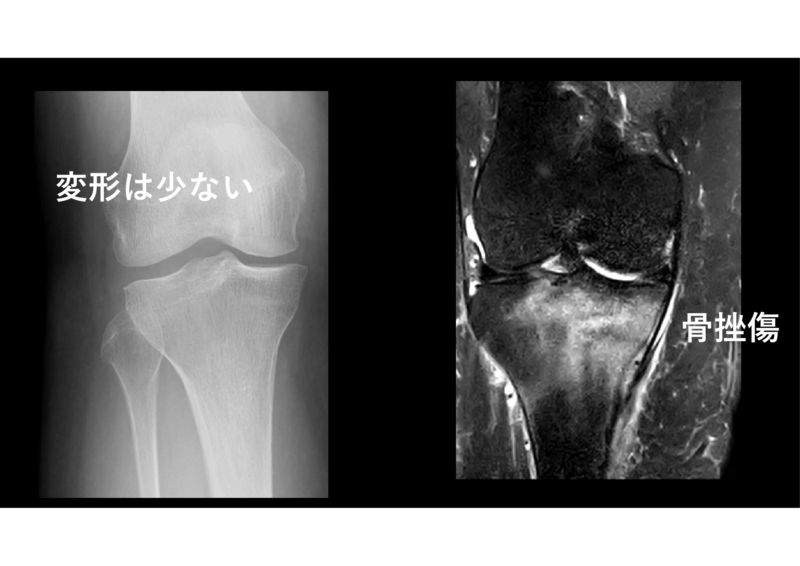

もう一つ最近のファインプレー

レントゲンで変形の強くない患者さんに膝のMRIを行いました。私の判断です。膝ですから100%査定されるのを覚悟の上です。何と脛骨に壊死を認めました。新しく来てくれた整形専門の先生に相談したら「負荷をかけるとつぶれる」、とのことで、松葉杖になりました。